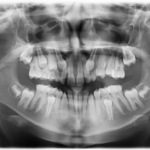

Mixoma odontogeno del mascellare in età pediatrica: caso clinico Premium

Il mixoma odontogeno è una rara neoplasia benigna che origina dal tessuto mesenchimale primitivo. Sebbene mostri crescita lenta e progressiva, può comportarsi in modo infiltrativo, mimando tumori maligni sia all’esame clinico che radiologico. Una diagnosi accurata si basa sulla valutazione istopatologica a causa della sua presentazione aspecifica. Questo articolo sottolinea l’importanza di una strategia multidisciplinare e di una gestione chirurgica precoce per garantire risultati ottimali e ridurre al minimo il rischio di recidiva.